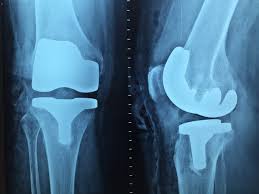

무릎 인공관절수술비용이 궁금하신가요? 퇴행성 관절염 등으로 무릎 인공관절 수술을 고려하는 분들이 많은데, 비용은 건강보험 여부, 병원급, 선택진료 옵션, 장비 사용(로봇) 등에 따라 크게 달라집니다. 국내 비용부터 의료관광 비용, 보험 적용 여부까지 자세히 알려드립니다.